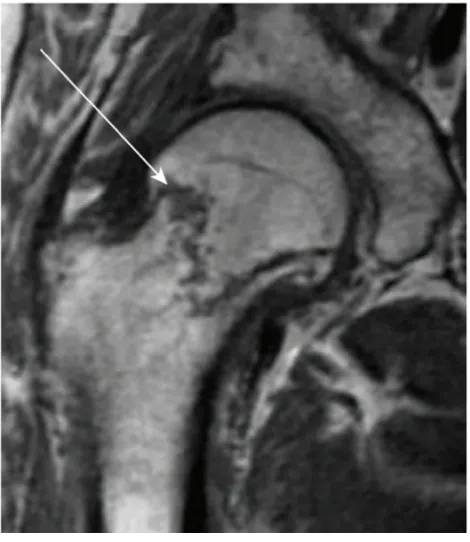

E3. Occult Hip Fractures

(1) X-ray에서 골절선이 발견되지 않으나 걸을 수 없거나 보행 시 심한 통증을 호소하는 경우 CT 또는 MRI (100% 민감도) 촬영해야 함

(2) Stress, incomplete, nondisplaced의 경우 몇 주후에도 x-ray로는 안 보일 수 있음

(3) 치료 : MRI 통한 배제 전까지는 weight-bearing 금지, 정형외과 외래 추적